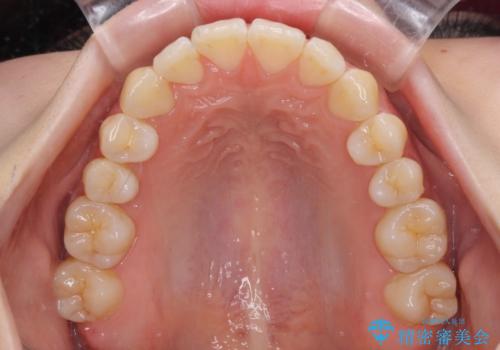

気になるデコボコとオープンバイト インビザラインでの矯正治療

- 前歯のデコボコと上下が開いていることを気にして来院された患者様です。

いわゆるオープンバイトは、インビザラインによる治療が適しているため、インビザラインにて治療を行うこととしました。